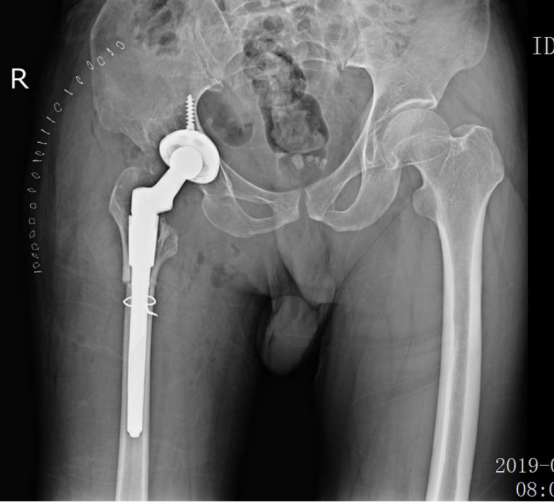

惠州三院關(guān)節(jié)外科崔鳳金主任在會(huì)議上與其他會(huì)場(chǎng)專(zhuān)家分享了一例手術(shù)難度極高的病例,患者為64歲男性,主因是“右髖疼痛2年、加重半年多”入院治療。崔主任以患者現(xiàn)病史、既往史、體格檢查、x光片、CT、MR檢查等各項(xiàng)內(nèi)容為依據(jù),診斷患者是“右側(cè)髖關(guān)節(jié)發(fā)育不良”,并把手術(shù)方案分享給各大會(huì)場(chǎng)教授進(jìn)行點(diǎn)評(píng)。各會(huì)場(chǎng)教授對(duì)于惠州三院提出的特殊病例紛紛提出了自己的看法和建議,對(duì)病例的多種可能性進(jìn)行討論,意見(jiàn)紛呈,現(xiàn)場(chǎng)氣氛高漲。

手術(shù)前

手術(shù)后

這是一例四度DDH的患者。這類(lèi)患者施行全髖關(guān)節(jié)置換手術(shù),是骨科帶有標(biāo)志性意義的高難度手術(shù)之一?;葜萑宏P(guān)節(jié)外科專(zhuān)家經(jīng)過(guò)術(shù)前認(rèn)真討論和規(guī)劃,順利地為患者實(shí)施了手術(shù),術(shù)后患者如期下地行走,解決了困擾患者多年的髖部疼痛和跛行的問(wèn)題。近年來(lái),隨著骨科技術(shù)水平的不斷提高,社會(huì)影響力越來(lái)越大,越來(lái)越多的骨科患者來(lái)這里求醫(yī)。一臺(tái)臺(tái)精準(zhǔn)的手術(shù),為一個(gè)個(gè)長(zhǎng)期受病痛困擾的家庭帶來(lái)曙光。